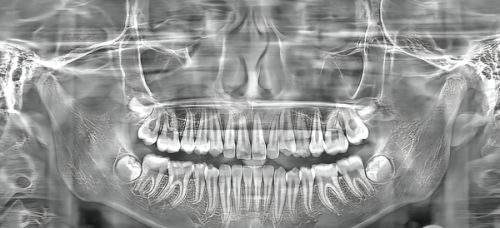

精良设备:医院在硬件投入上不遗余力,引进了如德国Kavo种植系统、意大利NewTom口腔CBCT、韩国怡友全景机、正畸口扫仪等设备,为精细诊疗提供了有力支持。消毒流程通过ISO认证,诊室采用透明化设计,患者可直接观察器械处理过程,从源头降低感染风险。